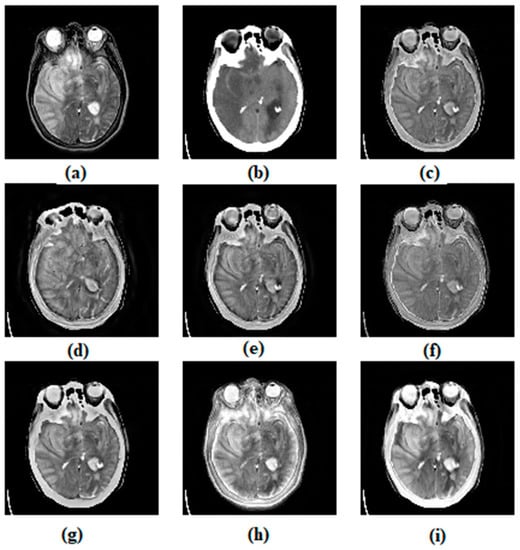

3.1. Subjective Assessment

| Metrics | Methods | ||||||

|---|---|---|---|---|---|---|---|

| ASR | CVT | DTCWT | MSVD | CSMCA | NSST | Proposed Method | |

| EI | 85.184 | 91.417 (1) | 88.853 | 77.183 | 87.219 | 81.907 | 90.390 (2) |

| MI | 3.948 (2) | 3.548 | 3.656 | 3.490 | 3.811 | 3.703 | 4.079 (1) |

| VIFF | 0.321 | 0.290 | 0.280 | 0.344 (2) | 0.319 | 0.267 | 0.406 (1) |

| 0.535 | 0.478 | 0.500 | 0.427 | 0.536 (2) | 0.373 | 0.538 (1) | |

| SSIM | 0.563 | 0.376 | 0.499 | 0.548 | 0.629 (2) | 0.520 | 0.697 (1) |

| AG | 8.561 | 9.140 (1) | 8.933 | 8.332 | 8.674 | 8.368 | 9.008 (2) |

| RMSE | 0.034 | 0.034 | 0.034 | 0.034 | 0.035 | 0.027 (2) | 0.020 |

| PSNR | 16.328 | 16.749 | 17.166 | 13.28 | 17.393 (2) | 13.976 | 21.342 (1) |